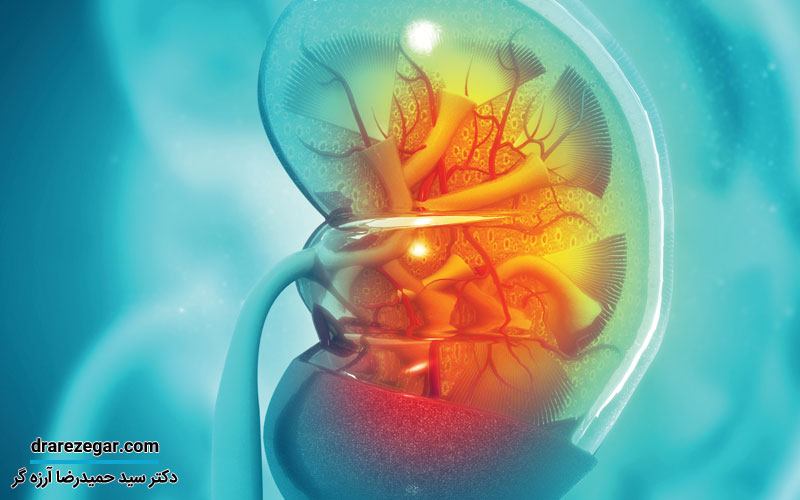

سنگ کلیه و سنگ حالب، مشکلی است که بسیاری از مردم به آن دچار هستند. احتمالاً همه ما در خانواده هایمان، فردی را می شناسیم که با این بیماری، درگیر است. اما چگونه می توان از ابتلا به این مشکل، جلوگیری کرد؟ آیا راهی قطعی برای پیشگیری از ساخت سنگ کلیه و سنگ حالب، وجود دارد؟ در ادامه این مطلب، قصد داریم تا به بررسی این دو پرسش و یافتن پاسخی برای آن ها، بپردازیم.